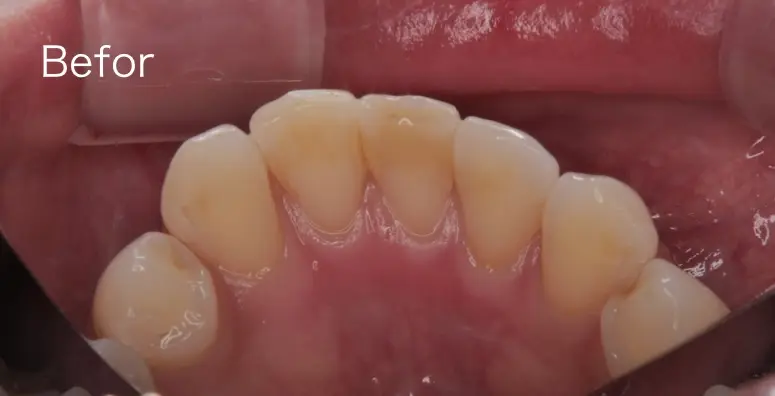

歯石を除去する前とした後の写真です。